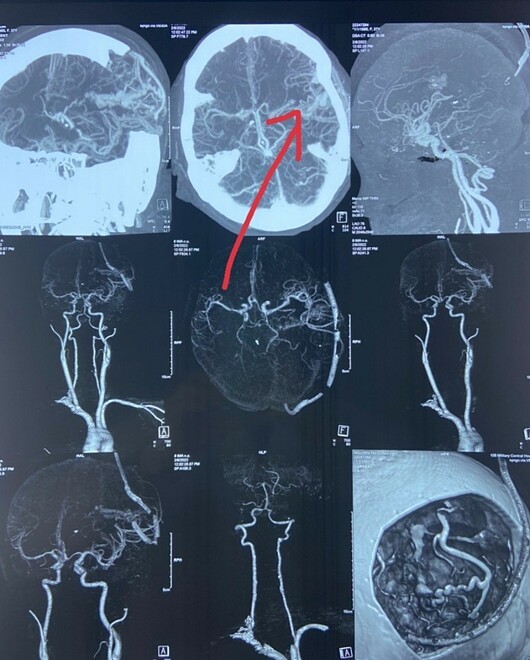

Bác sĩ Tạ Đức Thao (Khoa Đột quỵ) cho biết hình ảnh chụp CT sọ não và mạch máu não phát hiện bệnh nhân bị đột quỵ xuất huyết não do vỡ dị dạng mạch máu não. Bệnh nhân được kíp bác sĩ nút khối dị dạng mạch máu ngăn nguy cơ vỡ tái phát. Tuy nhiên, tình trạng bệnh nhân còn nặng, thở máy, hôn mê.

Dị dạng mạch máu não có thể bẩm sinh (AVM) hoặc hình thành theo thời gian (phình mạch não). Hai phương pháp khảo sát mạch não là chụp cộng hưởng từ mạch máu não và chụp cắt lớp vi tính mạch máu não là phổ biến nhất. Nếu phát hiện dị dạng mạch, các bác sĩ có thể điều trị nút mạch chủ động trước khi dị dạng bị vỡ. Hiện tại các bệnh viện từ tuyến tỉnh trở lên đều trang bị cả hai loại máy này, chi phí một lần chụp cũng không quá đắt tiền. Phần lớn bệnh nhân dị dạng mạch máu não không có triệu chứng, phát hiện khi dị dạng mạch đã vỡ, điều trị khó khăn, nếu không cấp cứu kịp thời gây nguy hiểm tính mạng.